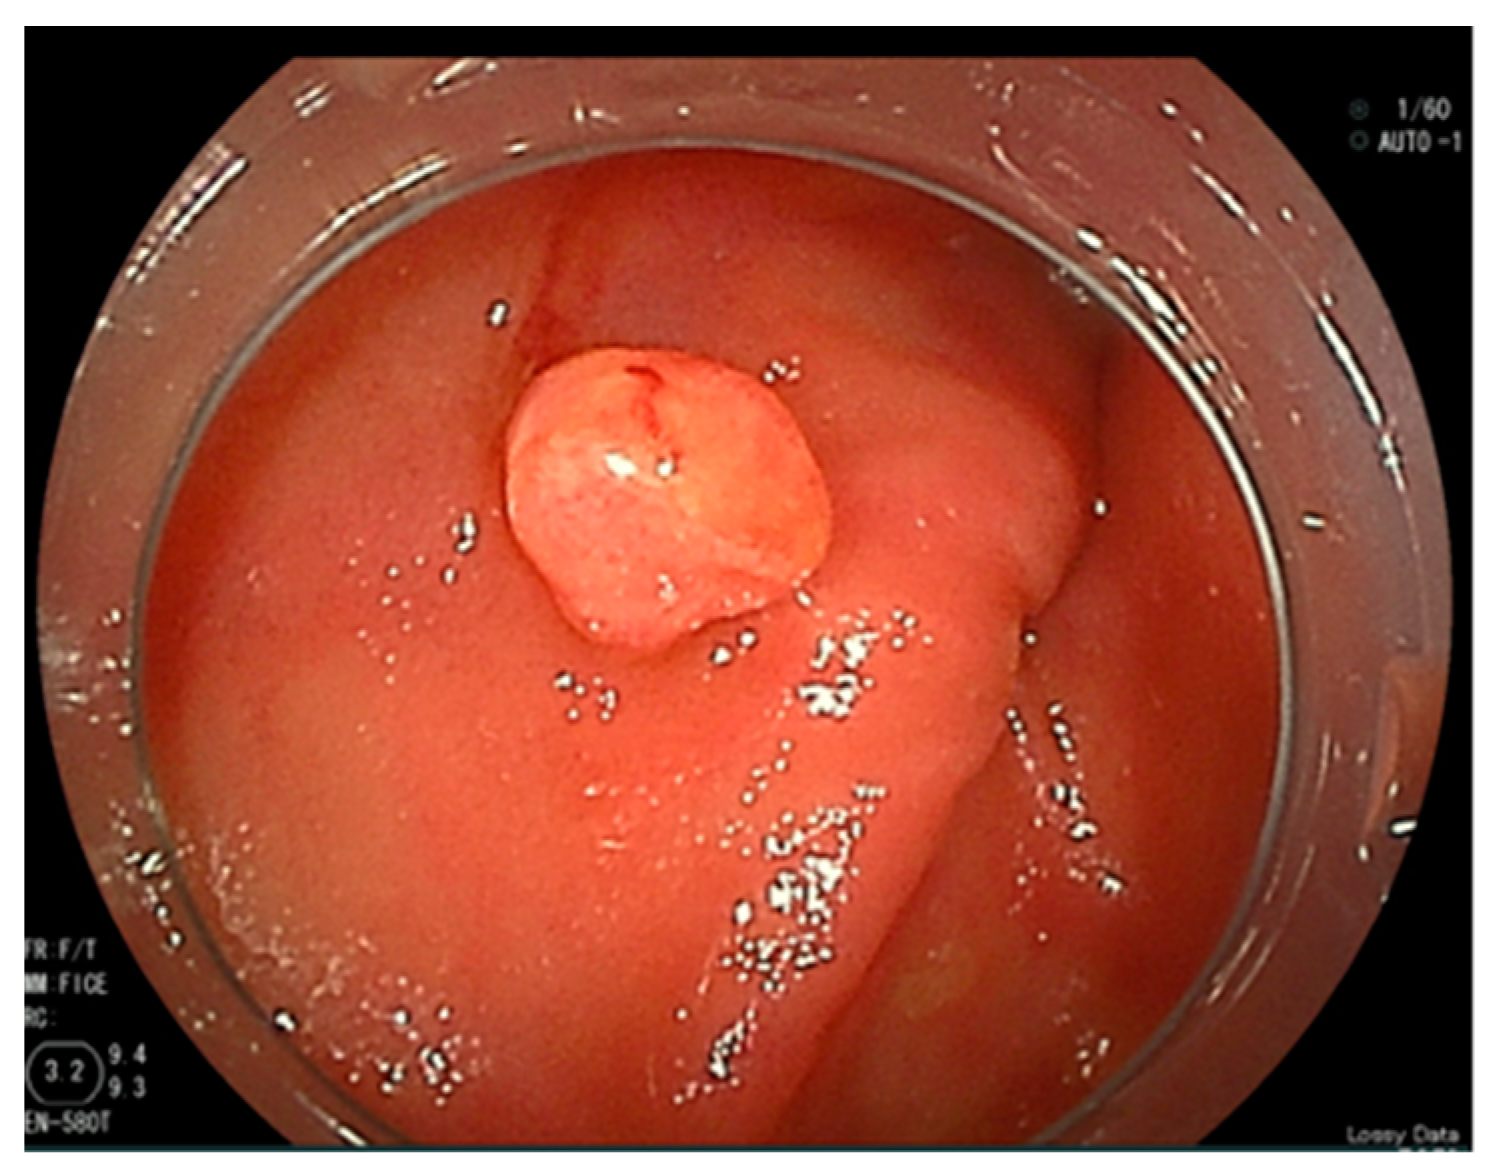

Abdominal contrast-enhanced computed tomography, gastroscopy, and colonoscopy were performed; however, no evidence of bleeding was found. An SBCE (PillCam® SB3, Covidien Japan Ltd., Tokyo, Japan) revealed a reddish polypoid lesion with blood oozing into the jejunum (Figure 1). We performed an antegrade DBE (EN-580T®, Fujifilm, Tokyo, Japan) to detect the cause of the bleeding and achieved endoscopic hemostasis. The DBE revealed a 5 mm sized protrusion into the jejunum about 200 cm distal from the Treitz ligament (Figure 2). The surface of the lesion was covered with mucus and slightly reddish compared to the surrounding mucosa.

Figure 2. A reddish protrusion in the jejunum as found by double-balloon endoscopy.